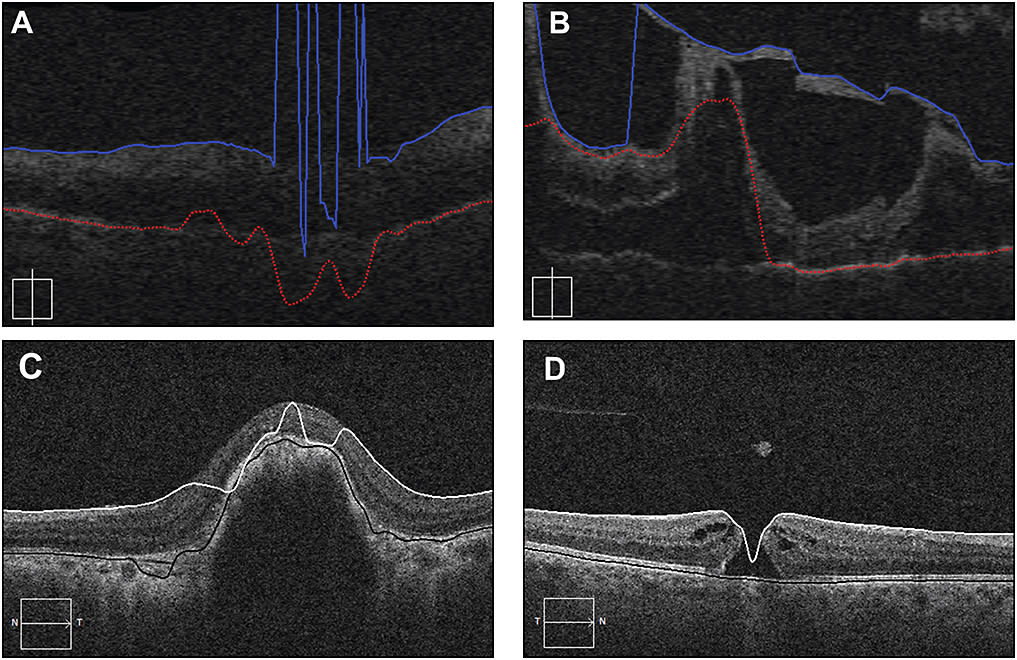

Unfortunately, in pathologic states, which are obviously the most critical scans for clinicians, automated segmentations can become unreliable (Figure 2, page 40). Lee and colleagues presented their experience recruiting untrained AMT users to trace the layers of the retina on several markedly abnormal OCTs at the 2014 ARVO annual meeting.10

Figure 2. An assortment of OCT segmentation errors made by automated software. A) In this scan with poor signal strength centrally, the internal limiting membrane and retinal pigment epithelium are essentially completely lost. B) In this scan from diabetic tractional detachment, a thick posterior hyaloid tractional membrane is mistaken for the ILM and the algorithm loses the RPE on the left half of the scan. C) This patient with exudative AMD has a scan in which the ILM tracing jumps back and forth from the ILM to the RPE. This type of error will be propagated to the thickness map. D) In this patient with a full-thickness macular hole, the algorithm cannot detect the discontinuity of the ILM inherent in this disease.

This group found that they were able to generate reliable tracings at a very low cost. Each tracing took the workers an average of slightly more than 30 seconds, and it was performed for $0.01. The authors reported that the AMT workers succeeded specifically where the automated algorithms had failed.